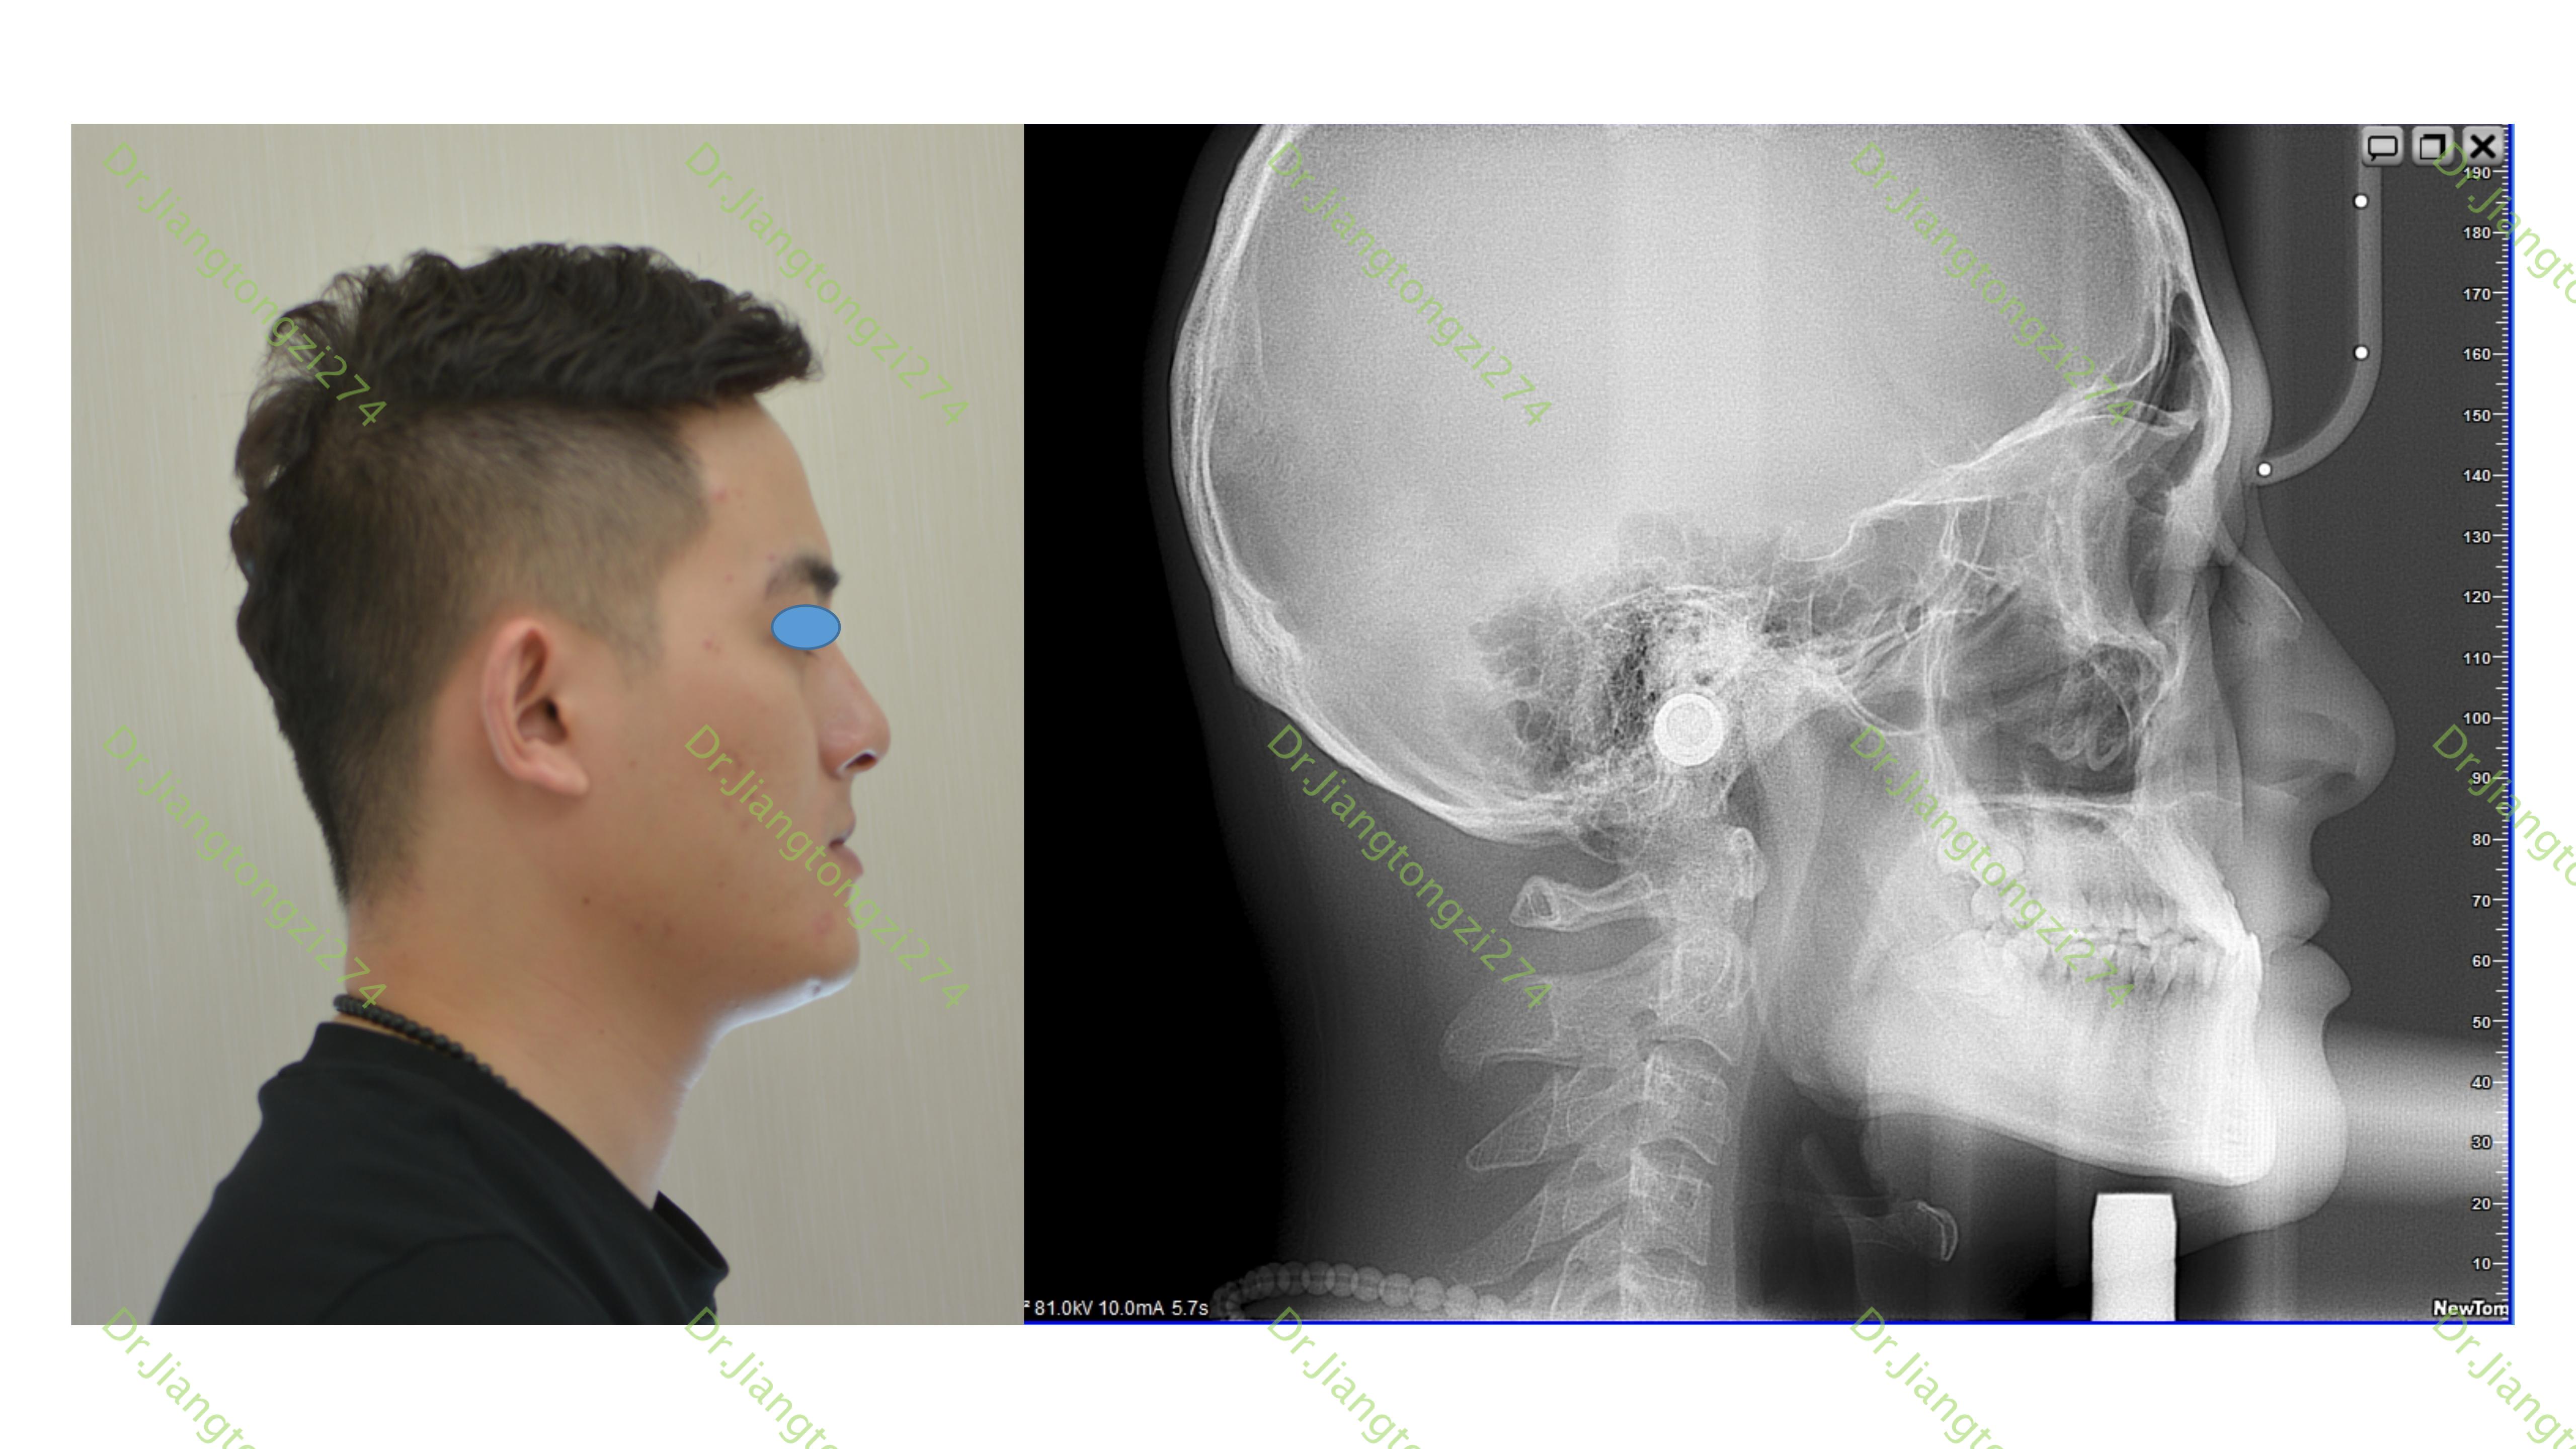

骨性iii类错合畸形病例矫治过程